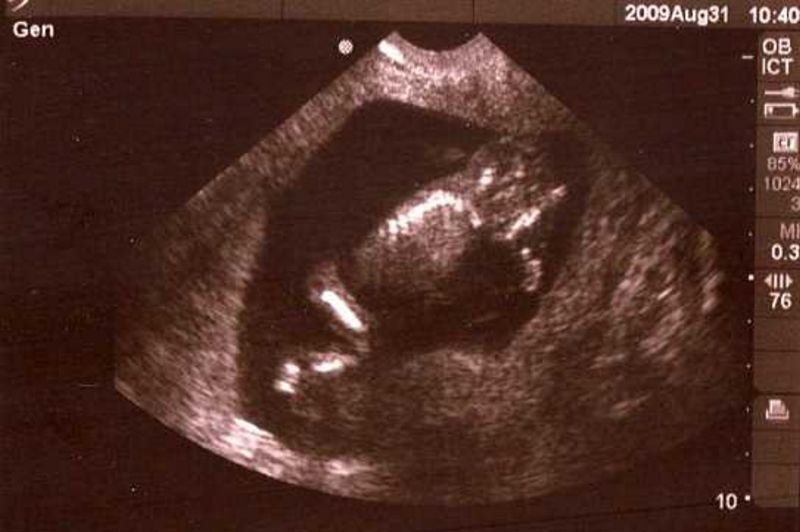

Fetal